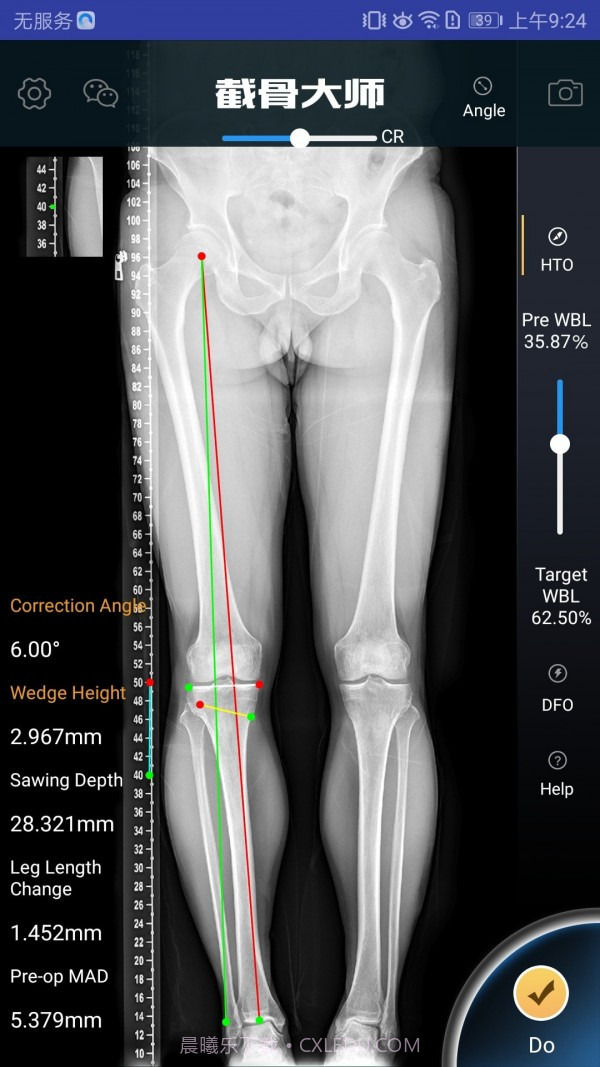

截骨大师真的是个宝藏APP,特别适合骨科医生和医疗人员使用。它的手术模拟功能超级高效,能让医生在手术前清晰地了解手术效果,避免在实际操作中出现失误。而且,它的参数计算非常精准,真的是为医生的工作提供了很大的帮助。用这款软件,你不仅能节省大量准备时间,还能显著提高手术的成功率,对患者的治疗也有很大保障。作为医生,这款工具简直是必不可少的选择!

精准的参数计算,避免手术中的失误

高效的手术模拟功能,医生可以直观了解手术效果

精准的算法支持,确保每个计算结果都可靠